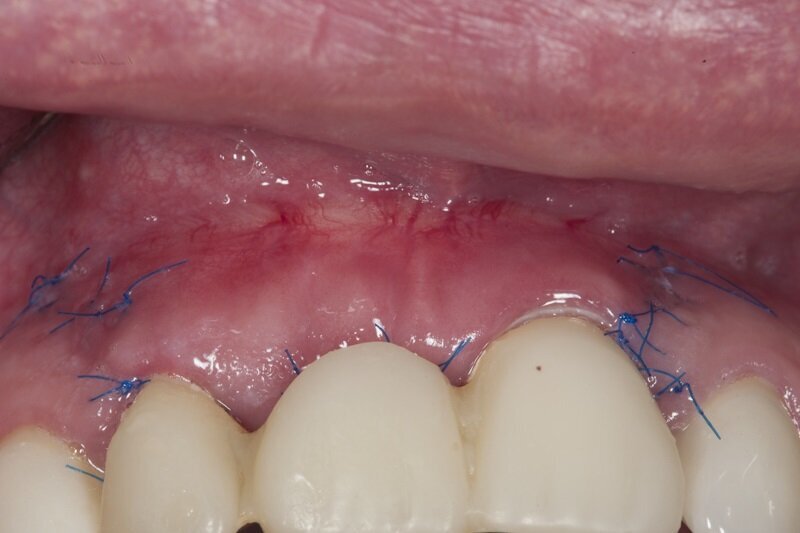

Po zabiegu pacjentka nie przyjmowała żadnych leków, także przeciwbólowych. Zgłosiła się na wizytę kontrolną 7 dni później. Badanie wewnątrzustne wykazało pokrycie nabłonkiem odsłoniętej w czasie zabiegu okostnej i znaczny stopień wygojenia rany (Ryc. 8), co umożliwiło usunięcie szwów.

Ryc. 9_Stan 7 dni po zabiegu.